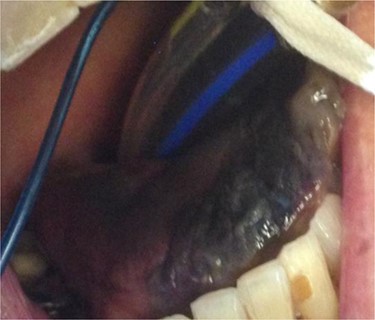

At Day 34, the patient was taken back to theatre by the maxillofacial team. Much of the anterior and part of the posterior third of the dorsum of the tongue was necrotic (Fig. 2). The necrotic area was removed, and the tongue debrided to healthy tissue.